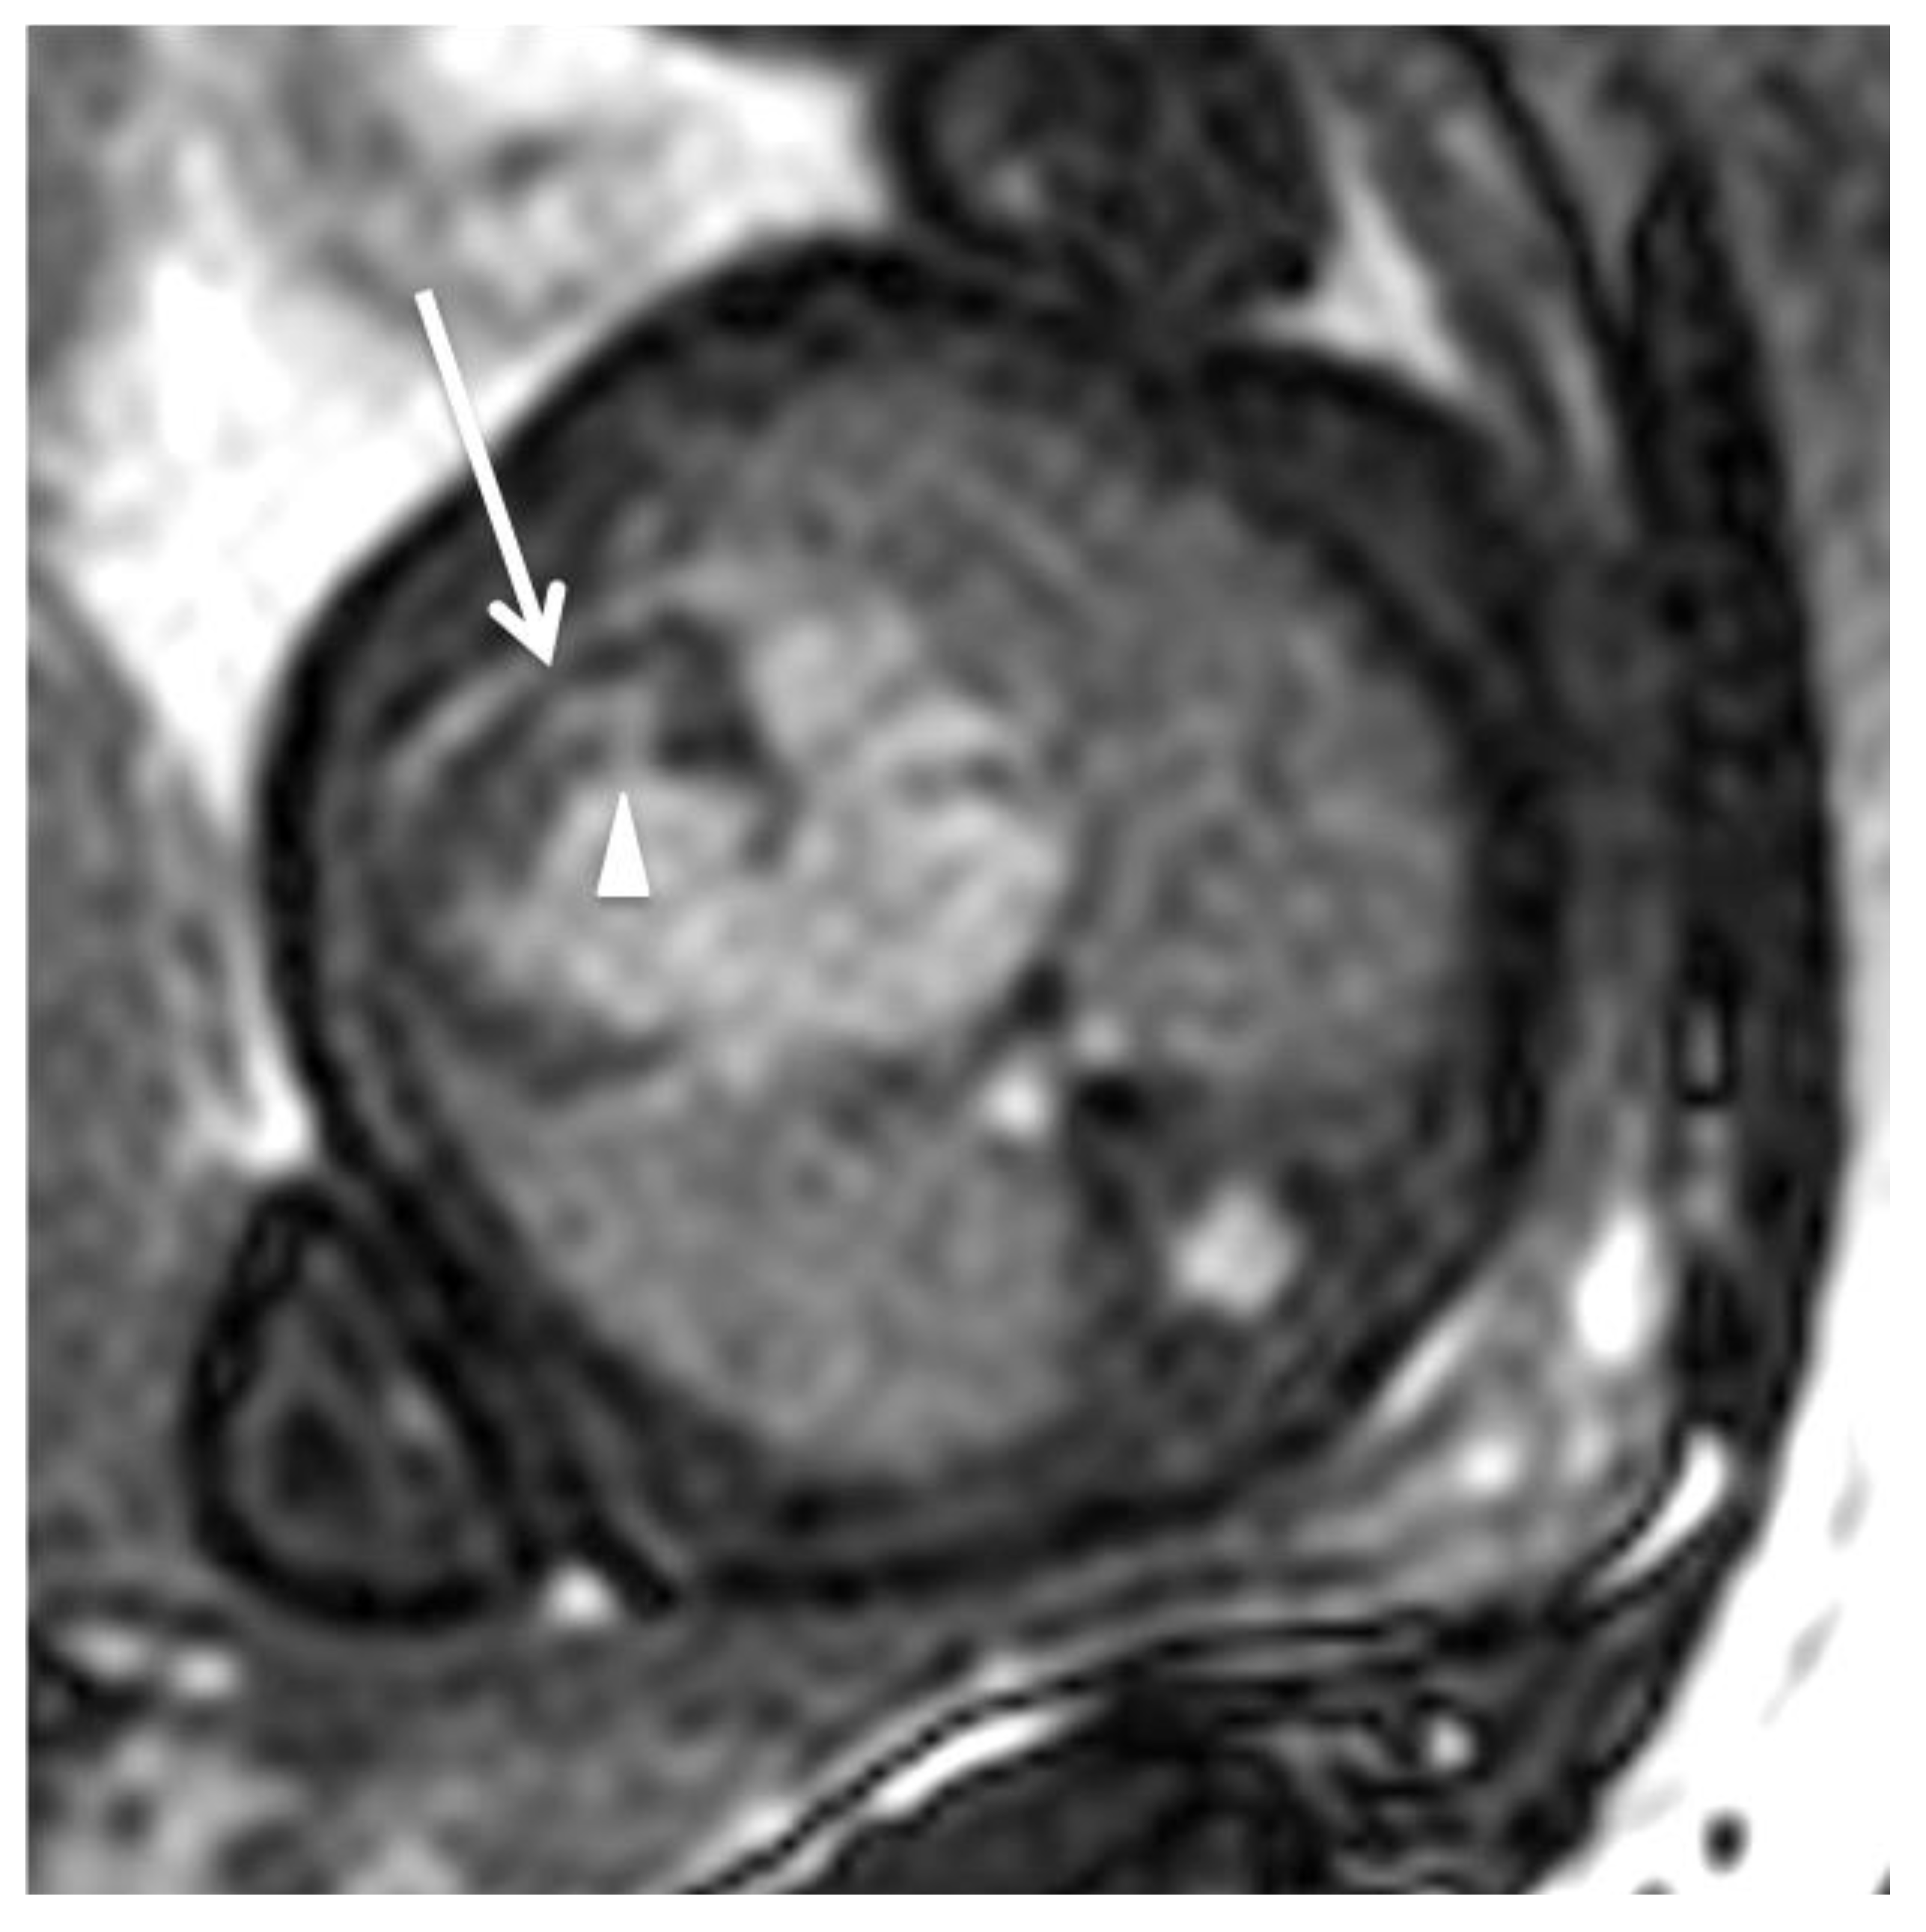

The Evolution and Developing Importance of Fetal Magnetic Resonance Imaging in the Diagnosis of Congenital Cardiac Anomalies: A Systematic Review

2. Fetal Cardiac MRI Techniques

3. Current Potential and Clinical Application of Fetal Cardiac MRI